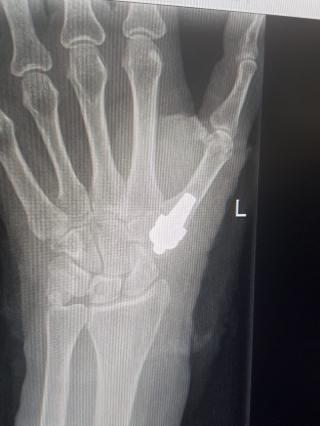

Женщина 55 лет с выраженными болями в запястно- пястном суставе, затруднение в самообслуживании, постоянные боли в кисти. Боли полностью прошли через 7 дней после операции. Сила хвата кисти увеличилась. Увеличилась амплитуда движений в самой кисти и в оперированном суставе.